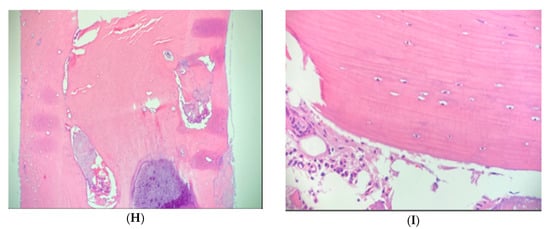

Figure 4. (AI) Case 2. Pelvic axial CT shows enlargement, atypical central radiolucency and osteoid osteoma mimicking BI in a patient with osteopoikilosis. (AC) Initial CT shows a right sacral lesion (white arrow) measuring 8 mm, left anterior iliac centrally radiolucent less sclerotic lesion (black arrow) and sclerotic bone lesion in the left posterior ilium (red arrow) near the SI joint. (D,E) Repeat CT 5-years later shows enlargement to 18 mm in right sacrum (white arrow), stable centrally radiolucent left anterior iliac lesion (black arrow) and left posterior iliac lesion (red arrow) correlating with the patient’s pain, TTP (tenderness to palpation) and increased BS (bone scan) uptake. (F) NM whole body bone scintigraphy demonstrating increased uptake in the left posterior ilium adjacent to the SI joint. (G) Higher magnification emphasizes increased uptake. Given the atypical features, biopsies of the right sacrum (due to enlargement and increased activity on BS) and left posterior ilium (due to pain and local tenderness) were performed. These established the diagnoses of atypical bone island and osteoid osteoma (OO), respectively. Radiofrequency ablation of the OO resolved her symptoms. Left anterior iliac lesion was diagnosed clinically as BI. (H,I) Case 2. Hematoxylin and eosin (H&E) stain of right sacral bone biopsy, establishing a diagnosis of atypical bone island. (H) Magnification 10× (low power view) of the core biopsy showing cortical type bone. (I) Magnification 40× (high power view) of the specimen, displaying lamellar bone with small osteocytes and normal marrow components.